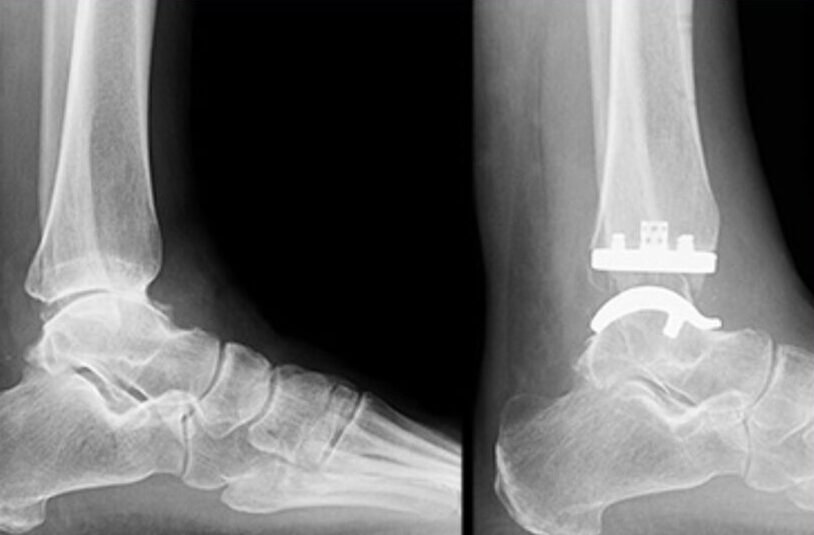

Total ankle replacement, also known as total ankle arthroplasty, is a surgical procedure designed to treat severe ankle arthritis by replacing the damaged joint surfaces with artificial components. This procedure aims to reduce pain, restore joint function, and improve overall ankle mobility. Total ankle replacement is considered an alternative to ankle fusion surgery and is suitable for select patients based on their condition and individual needs.

3. Total Ankle Replacement Surgery: During the surgical procedure, our skilled surgeons will make an incision and carefully remove the damaged joint surfaces. The artificial components will be precisely positioned and fixed to recreate the natural movement of the ankle joint. The type of implant used may vary based on factors such as your age, activity level, and the extent of joint damage. Our surgeons utilize advanced techniques to ensure optimal placement and stability of the implant.